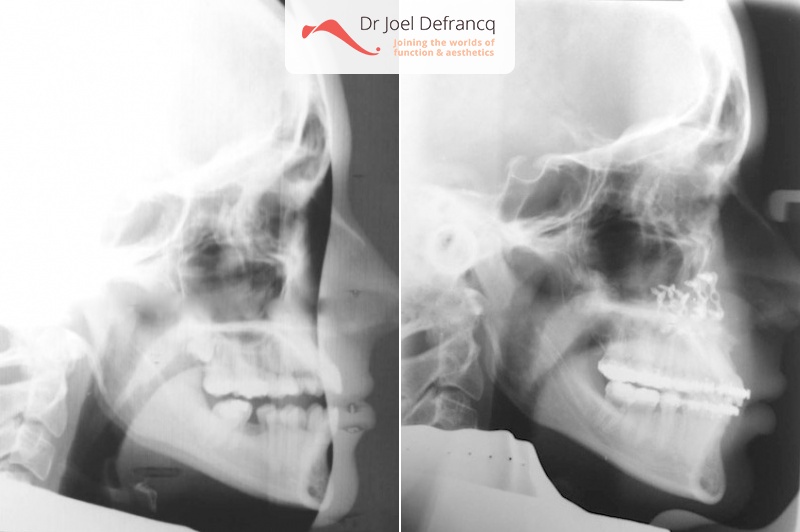

Diagnose van het gezicht

- Te korte bovenkaak

Kaakchirurgie

- Vertikale verlenging bovenkaak (Le Fort I)